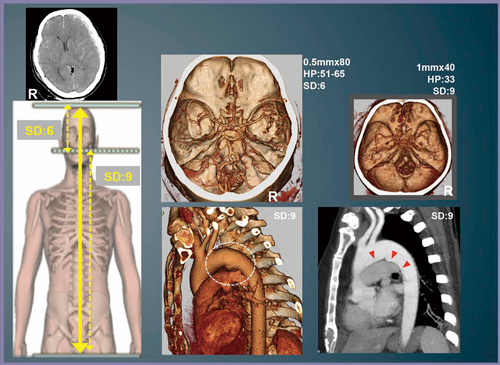

頸部以下の外傷全身CT Panscanが可能になったことで,次に頭部を含めたPanscanの要望が出てきた。頸部以下のPanscan造影プロトコルは,1mm×40スライス,SD9,ヘリカルピッチ(HP)33を使用しているが,同一プロトコルでは線量不足により頭頸部CTAの画質が低下し,頭蓋内の脳血管の描出が不十分となる。そこで,Aquilion PRIMEに搭載されているバリアブルヘリカルピッチスキャン(vHP)の使用を検討した。

vHPは,スキャン中に天板を停止することなくヘリカルピッチを変更できる機能で,一般的には心電図同期の冠動脈CTAと大動脈を1回のスキャンで撮影する際などに使われている(図1)。このvHP機能を応用して,頭部は低ヘリカルピッチで撮影し,体幹部を高ヘリカルピッチで撮影する方法で,脳血管の描出能の向上が可能かどうか検討した。

まず,撮影スライス厚とヘリカルピッチの組み合わせによる,アーチファクトの影響を検証した(図2)。体幹部で使用している1mm×40スライス,HP33では強いアーチファクトが認められたため,アーチファクト抑制と画質向上の臨床的なメリットの方が上回る0.5mm×80を選択し,vHP使用時の造影CT Panscanプロトコルを図3のように決定した。

60歳,女性。原付バイクでの交通外傷で救急搬送された。救急外来搬入時,JCS(意識レベル)300,瞳孔散大にて,気管挿管後,生命を脅かす中枢神経障害(切迫するD)があり,Secondary Surveyの最初に頭部CTを施行した。頭部のコンベンショナルCT(図4左上)では,左急性硬膜下血腫,外傷性SAH,脳挫傷,頭蓋底骨折を認めた。続いて,頭頂から骨盤まで,新しい外傷CTプロトコルを適用したvHPによるPanscanを行った(図4)。体幹部では,大動脈損傷の好発部位である大動脈峡部に膨らみを認め損傷を疑ったが,MPR像で周囲に血腫がないことが確認でき,大動脈損傷を否定することができた。脳血管については,以前の1mm×40の画像(図4右上)に比べて画質が改善されている(図4中上)。右側は末梢血管まで描出されているが,左側は血腫があり,脳圧が高く,末梢血管が圧迫されていることが確認できた。